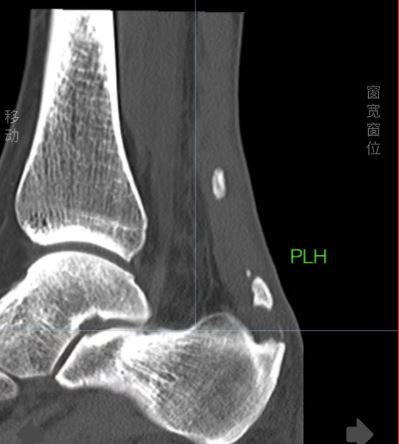

跟腱钙化是肌腱钙盐沉积导致,钙化的跟腱在X光下会表现为高亮度,和骨骼的亮度是相接近的。如果患者长时间进行剧烈运动,或进行繁重体力劳动等,都容易反复牵拉跟腱部位的胶原纤维,从而引起局部组织韧带损伤,出现跟腱钙化。在出现跟腱钙化后,可能表现为不能长时间站立、走路疼痛、跟腱水肿等症状

。